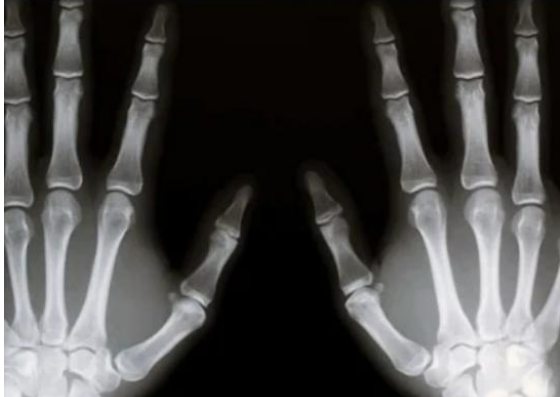

Rendgenska snimka je obično prvi korak i može pokazati promjene u strukturi kostiju. Magnetska rezonancija (MR) ili kompjuterizirana tomografija (CT) koriste se za točniju procjenu, ovi uređaji omogućuju točno određivanje veličine i lokacije tumora. Međutim, najvažniji dio dijagnoze je biopsija, koja daje uzorak tkiva koji se analizira mikroskopom. Ovaj postupak je ključan za utvrđivanje prisutnosti stanica raka, a dodatni laboratorijski testovi koji se mogu provesti tijekom napredovanja bolesti često su važni u praćenju napredovanja bolesti.